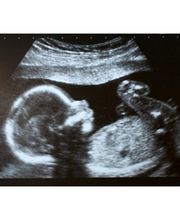

Il Dr. Pollina Salvatore è medico chirurgo specialista in ostetricia e ginecologia. Esercita la professione medica presso il proprio studio ubicato a Trapani, eseguendo interventi di chirurgia ginecologica presso la casa di cura S. Anna di Erice(Casa Santa), mediante le moderne tecniche laparoscopiche e tradizionali, esegue tutti i metodi di fecondazione assistita dall'inseminazione, alla FIVET, GIFT, ICSI per le coppie che hanno problemi di sterilità. Monitoraggio della gravidanza, ecografia morfologica e 4D, diagnosi prenatale(screening I° trimestre, amniocentesi, ecocardiografia fetale). Assiste al parto con le tecniche naturali per una nascita più dolce mediante il parto in acqua, con la musica, nella camera familiare, con libertà di movimento.